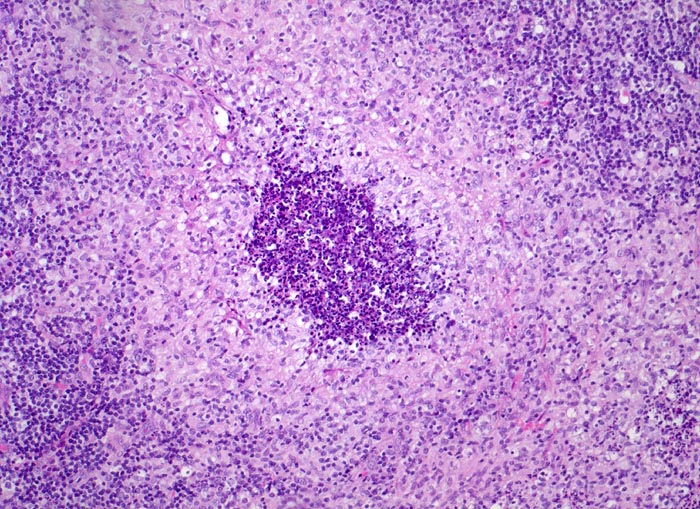

PathoPic ID 3923 - retikulozytär-abszedierende Lymphadenitis bei Katzenkratzkrankheit

retikulozytär-abszedierende Lymphadenitis bei Katzenkratzkrankheit

Entzündung infektiös

Lymphknoten, Axilla

Lymphatische Gewebe, KM, Milz

Granulom mit zentraler Nekrosezone mit massenhaft neutrophilen

Granulozyten gesäumt von

Histiozyten (Retikulumzellen).

Nachweis von kleinen pleomorphen Bakterien

Druckschmerzhafte Lymphknotenvergrösserung in der rechten Axilla 2 Wochen nachdem der Patient von seiner Katze an der rechten Hand gekratzt wurde.

Keine käsige Nekrose wie bei Tbc.

200